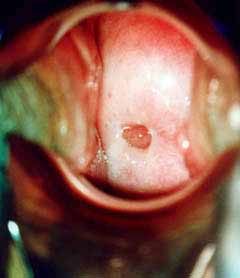

Κολποσκοπικές εικονες για τις αναγκες του forum.